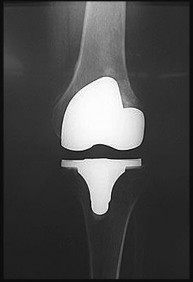

Question 16

A 65-year-old man presents with anterior knee pain and a feeling of instability during stair climbing 1 year after a primary total knee arthroplasty.

Examination reveals a lateral patellar tilt. CT scan is performed to evaluate component rotation. Which of the following errors in component positioning is most likely responsible for his symptoms?

Explanation

Internal rotation of the femoral component or the tibial component increases the Q angle, leading to lateral patellar maltracking, lateral patellar tilt, and anterior knee pain. External rotation of the components generally improves patellar tracking.